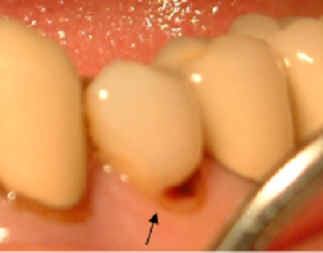

【牙周病】